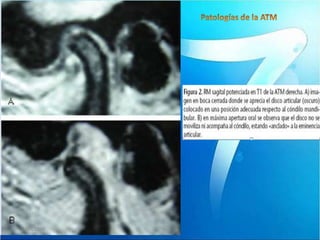

Boca abierta

Boca cerrada